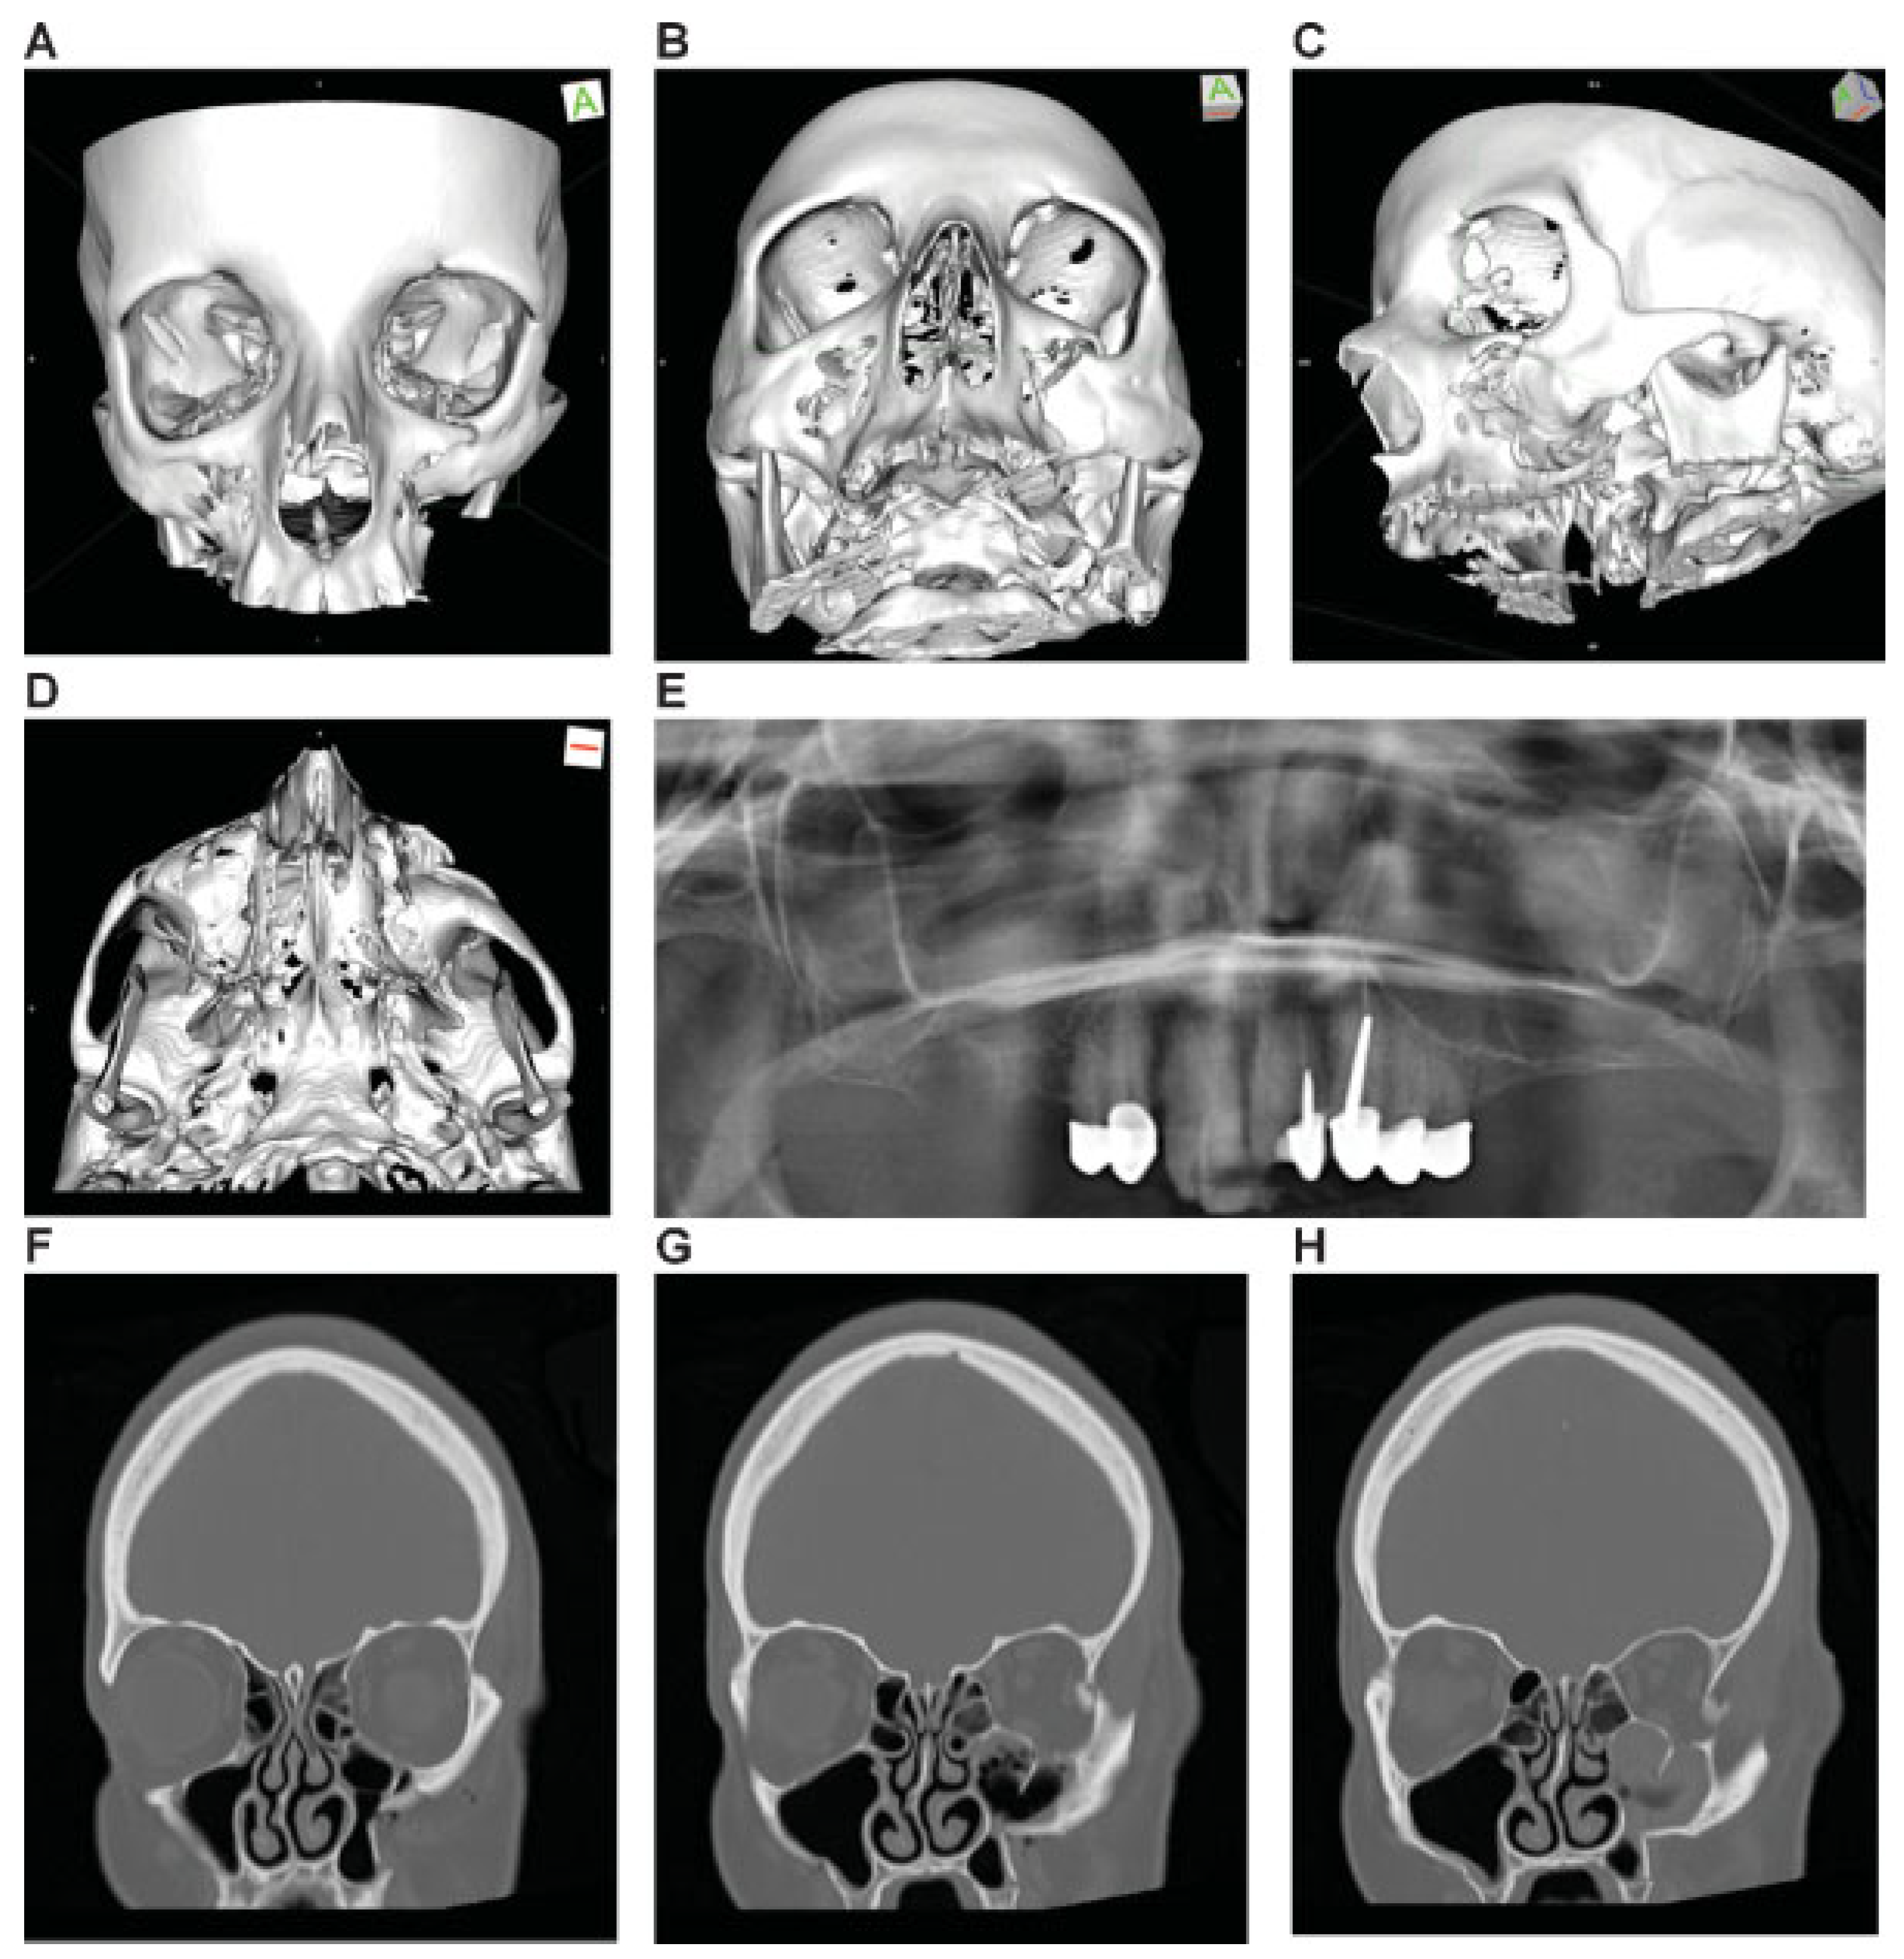

Figure 7.

Zygoma Fracture left with dorsocranial displacement and antral impaction. Three-dimensional (3D) computed tomographic (CT) scans—(A) frontal view, (B) caudofrontal view, (C) oblique lateral view left, (D) caudolateral view; panoramic X-ray—(E) OPT. (F–I) coronal CT scans; (J-M) axial CT scans: sagittal CT scans—(N) next to medial orbit wall left, (O) at the level of medial orbital floor left, (P) just medial to inferior orbital fissure left. (Q) Level 3 Code : 92 m.Oil.I1.Z0i - 93 m.M0, Orbit (left)R(li).W1(li)2(li). This case example CMTR-92-102 is made available electronically for viewing using the AOCOIAC software at www.aocmf.org/classification. Narrative description: Zygoma fracture left. Details: fracture following ZFS, fragmentation along ZSS with intermediate fracture extending into the greater wing of sphenoid and the orbital flange of the zygoma, single fracture-infraorbital process, multifragmentation of facial antral wall left, ZMC and tuber region (LCM), zygomatic arch fracture. Dentition (FDI): Lack of 18–15; 26–28. Maxillary alveolar process atrophy: severe displacement: cranial and dorsal displacement (translational), antral impaction (rotation around sagittal axis through zygomatic body). Internal orbit left: Involvement confined to anterior orbital section and midorbit—anterolateral inferior and lateral fragments in juxtaposition to inferior orbital fissure.